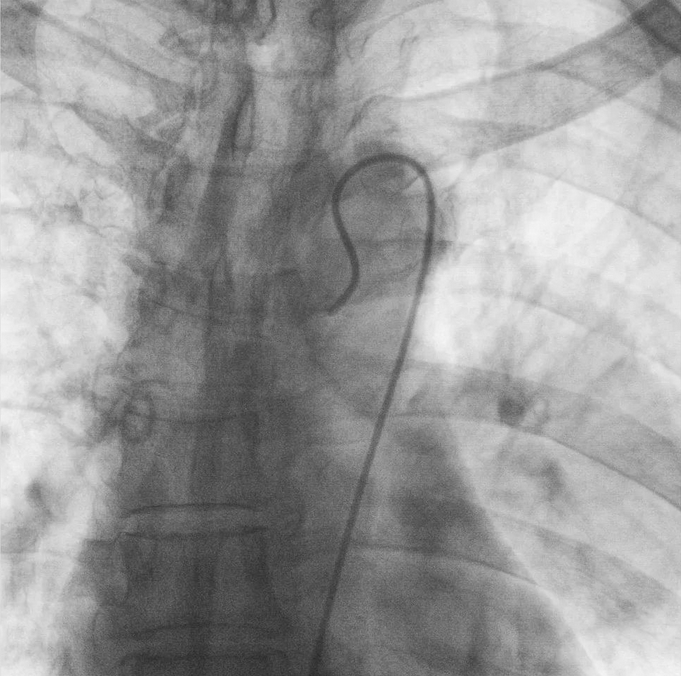

支氣管動脈栓塞+化療灌注術

在普愛醫(yī)療移動式平板介入中C影像的引導下,醫(yī)生為患者實施雙側支氣管動脈栓塞+化療灌注術。

在微導絲的配合下,先后分別超選擇①至3支左側支氣管動脈腫瘤供血動脈,經(jīng)微導管推注栓塞微粒球栓塞腫瘤動脈。栓塞結束后,再次用移動式平板介入中C做造影檢查,見腫瘤染色消失。